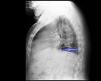

Upon his admission to the service, 24h from the onset of clinical symptoms, an emergency chest x-ray was taken, given the lack of symptom improvement after medical treatment. The lateral projection revealed a foreign body anterior to the ascending aorta (fig. 1), with no consolidation at the base of the right lung (fig. 2). Upper gastrointestinal endoscopy was performed that identified a bivalve shell in the mid-esophagus (fig. 3) with edematous and erythematous esophageal mucosa, and a small ulcer. The shell was extracted with a polypectomy basket, resolving the symptoms.